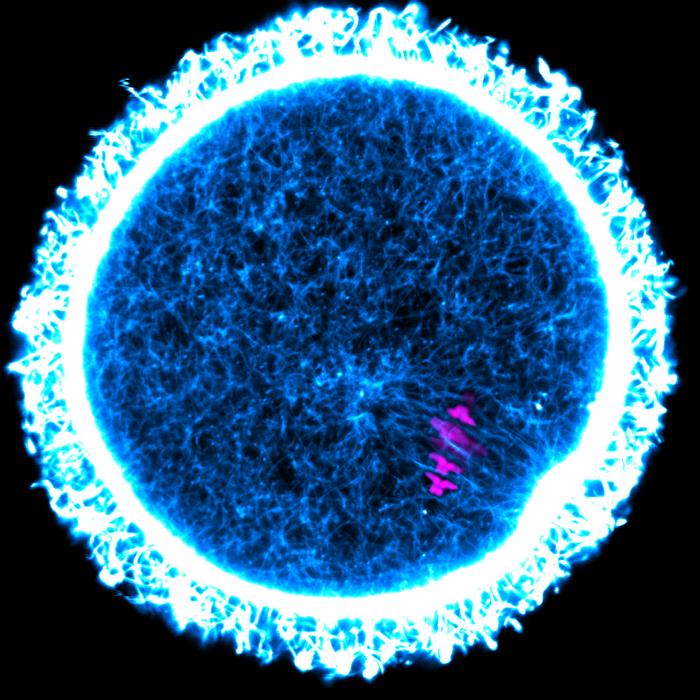

FEMALE MAMMALS ARE BORN WITH ALL THE EGG CELLS THEY WILL EVER HAVE IN THEIR OVARIES. SOME OF THESE CELLS THEREFORE LIVE FOR A LONG TIME – AND MUST REMAIN FUNCTIONAL THROUGHOUT THIS PERIOD. EXPERIMENTS WITH MICE HAVE NOW SHOWN: EXTREMELY LONG-LIVED PROTEINS IN THE OVARY CAN KEEP EGG CELLS HEALTHY AND PRESERVE FERTILITY FOR A LONG TIME. IN THE MOUSE EGG CELL SHOWN HERE, THE CHROMOSOMES ARE STAINED MAGENTA AND THE CYTOSKELETAL PROTEIN ACTIN IS STAINED BLUE AND WHITE.

view moreCREDIT: MELINA SCHUH / MAX PLANCK INSTITUTE FOR MULTIDISCIPLINARY SCIENCES